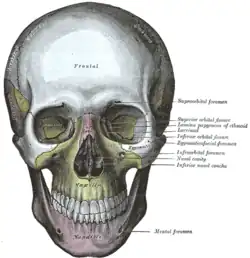

Vista frontal. Maxilar visível ao centro, em amarelo. | |

Cada metade da maxila fundida pode ser divida em:

- Corpo da maxila;

- Forame infraorbital;

- Seio maxilar e;

- Quatro processos:

- processo zigomático

- processo frontal

- Processo alveolar

- Processo palatino